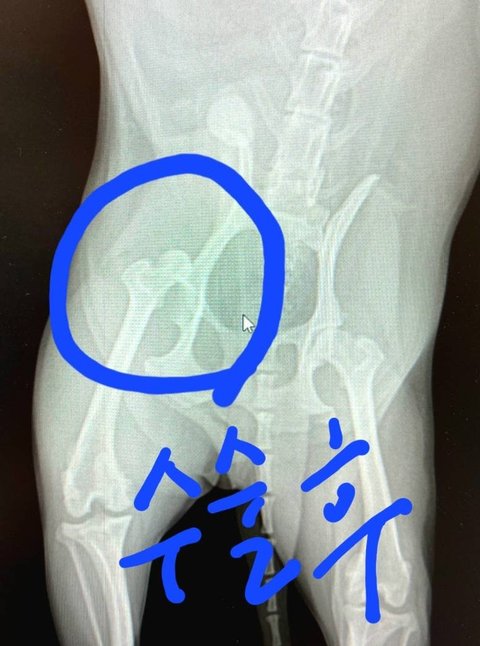

저희강아지가 대퇴골골절과 인대가 끊어져

받으니 외력에의한 대퇴골골절과 인대끊어짐소견으로 보인다며 바로 수술해야 한다해서 수술진행하고 이틀뒤 퇴원했습니다.